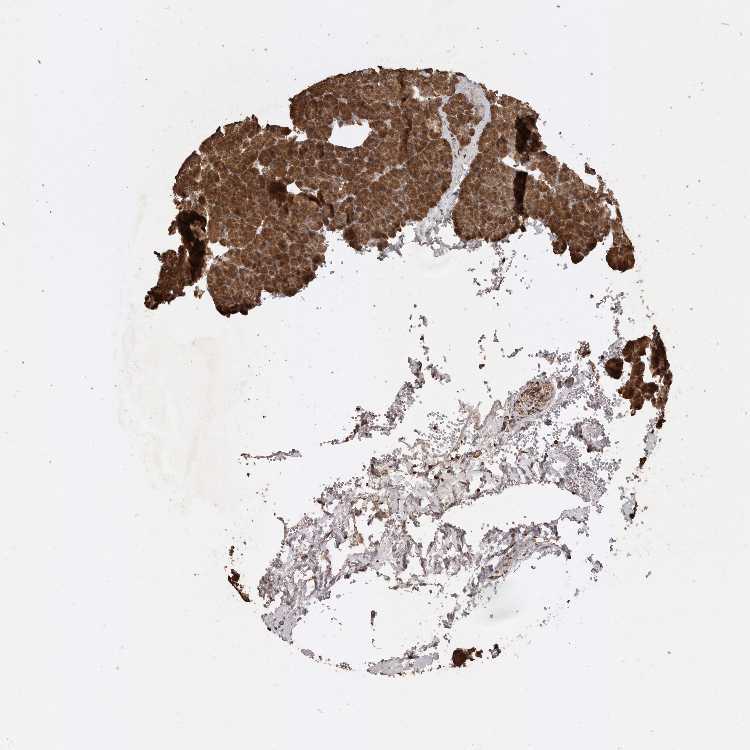

PANCREAS - Antibody stainingi

Antibody staining in the annotated cell types in the current human tissue is reported as not detected, low, medium, or high, based on conventional immunohistochemistry profiling in selected tissues. This score is based on the combination of the staining intensity and fraction of stained cells.

Each image is clickable and will lead to virtual microscopy that enables deeper exploration of all samples and also displays staining intensity scores, fraction scores and subcellular localization as well as patient and tissue information for each sample.

Antibody HPA001931Antibody CAB026191

Exocrine glandular cells LowHigh

Pancreatic endocrine cells LowMedium